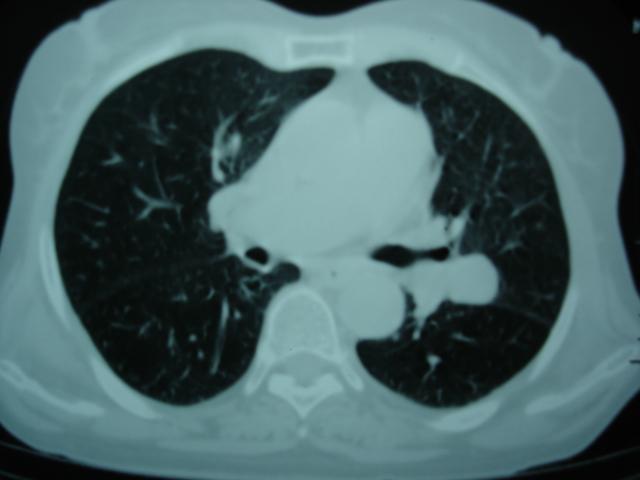

以下是引用卜一在2009-9-7 19:51:00的发言:[br][br] 1 左侧胸内甲状腺占位-多考虑甲状腺腺瘤! 2、左肺门占位-建议增强扫描以便明确性质。 3 慢支并感染! [br]

以下是引用shibing在2009-9-7 20:40:00的发言:[br]左侧胸内甲状腺占位-多考虑甲状腺腺瘤! 2、左肺门占位-建议增强扫描以便明确性质。 3 慢支并感染! [br]